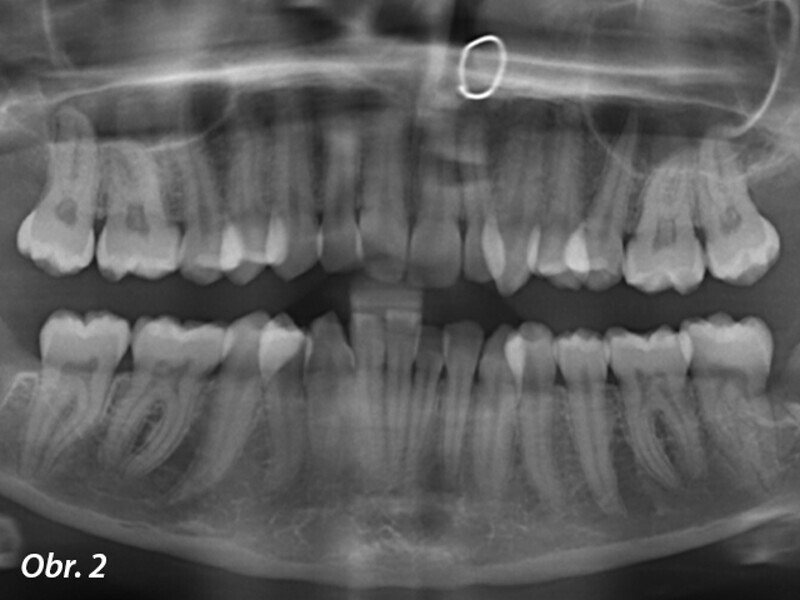

Ortodontická léčba komplexních případů malokluze pomocí průhledných alignerů